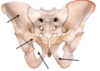

Pelvic Brim

Coccyx

Sacrum

Os coxae

Ilium

Acetabulum

Ischium

Pubis

Posterior/Anterior, Superior/Inferior Iliac Spines

Greater sciatic notch

Ischial spine

Lesser sciatic notch

Ischial tuberosity

Iliac Blade

Iliac Crest

Superior pubic ramus

Ischiopubic ramus

Obturator foramen

Pubic symphysis

Pelvis sexual dimorphisms?

Females:

Larger pelvic outlet

Wider subpubic angle

Sacrum tilted back